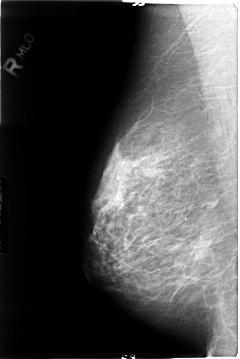

B_3042_1.RIGHT_MLO

ics_version 1.0

filename B-3042-1

DATE_OF_STUDY 27 12 1995

PATIENT_AGE 55

FILM_TYPE REGULAR

DENSITY 2

DATE_DIGITIZED 25 8 1997

DIGITIZER LUMISYS LASER

RIGHT_CC LINES 4784 PIXELS_PER_LINE 3080 BITS_PER_PIXEL 12 RESOLUTION 50 NON_OVERLAY

RIGHT_MLO LINES 4664 PIXELS_PER_LINE 3112 BITS_PER_PIXEL 12 RESOLUTION 50 NON_OVERLAY